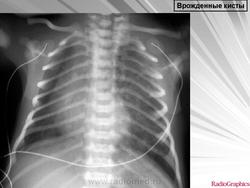

Легочные кисты.

Приложения:

1.ki_.slayd107.jpg2.ki_.slayd108.jpg3.ki_.slayd109.jpg